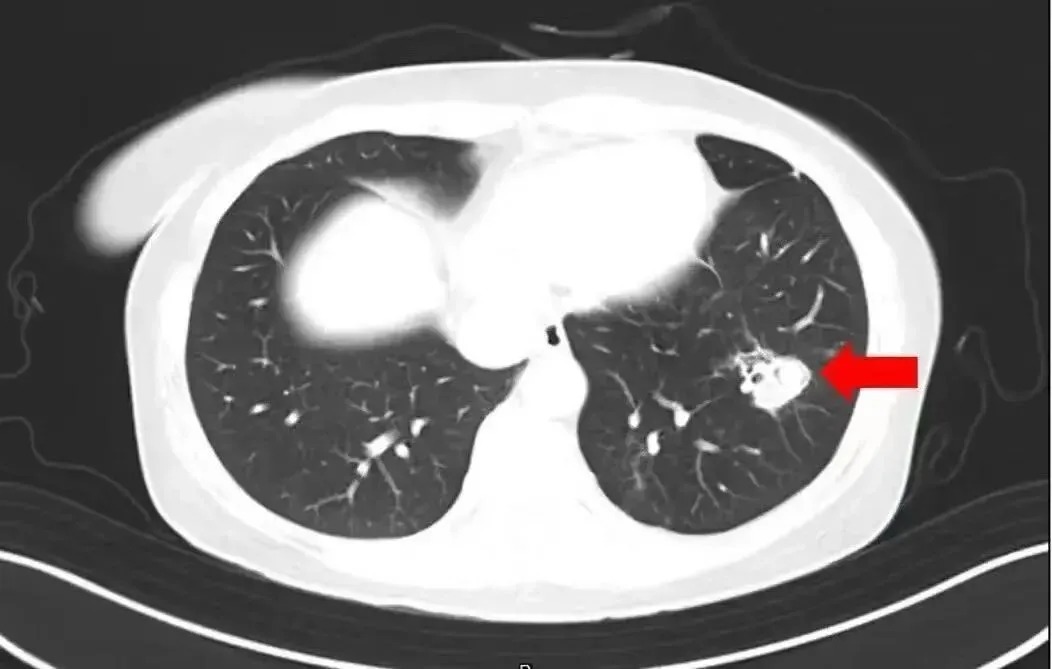

2025年1月,江苏扬州的张大爷为迎接春节开始大扫除,清扫过程中不慎吸入大量灰尘和霉菌孢子,导致哮喘发作。张大爷随即服用了常备的哮喘治疗药物,可症状反而逐渐加重。经检查,张大爷的肺部出现感染,确诊为肺曲霉病。

北京佑安医院感染综合科主任医师李侗曾介绍,对于免疫力低下的人,吸入了这些真菌,就会发病引起肺部的病变——曲霉肺炎。因为它是通过呼吸道感染的,进入血液后可以扩散到全身。大脑因为血供最丰富,所以也是真菌最容易侵犯的器官。